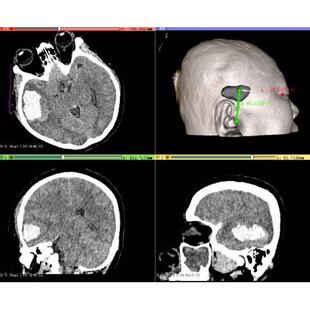

心胸外科三维可视化 CT数据三维重建 3D医学模型 dicom MRI 转STL

全身各部位影像数据(四肢骨、肝胆、心胸、泌尿)三维重建3D打印